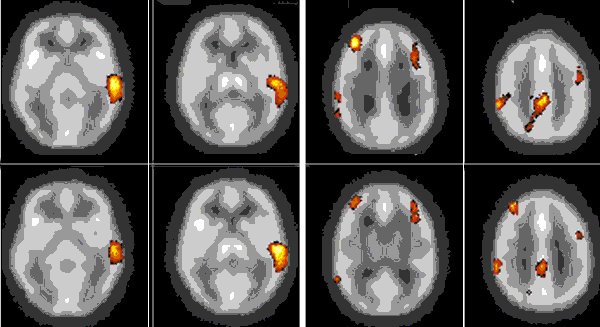

Именно наличие клиники во многом определяет возможности фундаментальных и прикладных исследований ИМЧ. Поэтому прежде всего несколько слов о ней. У нас прекрасные высококвалифицированные доктора и медсестры. Без этого нельзя: ведь мы на переднем крае, и нужна высочайшая квалификация, чтобы выполнять нерутинное, новое. У нас выполняются практически все стандартные манипуляции и наряду с ними и хирургическое лечение эпилепсии и паркинсонизма, проводятся психохирургические операции, в том числе и хирургическое лечение обусловленного героином обсессивно-компульсивного синдрома, знаменитая «пересадка мозга», точнее имплантация фетальной мозговой ткани, лечение магнитости-муляцией мозга, лечение афазии с помощью электростимуляции и многое другое. Накоплен десятилетний опыт клинических обследований с помощью позитронно-эмиссионной томографии. На рисунках приведена малая толика того, что может диагносцировать этот метод томографии. У нас лежат тяжелые больные, и мы стараемся помочь с помощью вышеперечисленных методов даже тогда, когда все остальные попытки были неудачны. Конечно, это удается не всегда. Но безграничных гарантий в лечении людей дать невозможно, а если кто-то дает их, это всегда вызывает очень серьезные сомнения.

Последствия острого нарушения мозгового кровообращения.

Зона, лишенная кровотока, типичной конусообразной формы (красные стрелки), характерной для последствий острого нарушения мозгового кровообращения. Впереди от нее зона снижения кровотока (белая стрелка).

Височная эпилепсия.

Выраженное снижение уровня потребления глюкозы (красные стрелки) в коре левой височной доли, где расположен очаг эпилепсии.

Дифференциальный диагноз опухолей головного мозга.

В зоне поражения (красные стрелки) не накапливается радиофармпрепарат, что исключает опухоль головного мозга.

Злокачественная опухоль головного мозга.

Очерченный очаг резко повышенного неоднородного накопления 11С-метионина в злокачественной опухоли левой височной доли (красные стрелки), которая неотчетливо контурировалась на магнитно-резонансных томограммах.